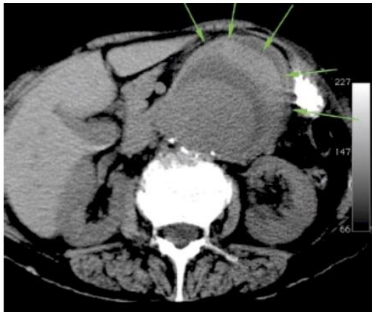

A angioTC foi o maior avanço no diagnóstico das patologias da aorta abdominal dos últimos 15 anos.

O cirurgião vascular deverá dominar este método de diagnóstico por imagem que poderá ser útil tanto no diagnóstico como no planejamento do tratamento, um dos sinais de ruptura é visibilizado na figura acima, que sinal é esse?